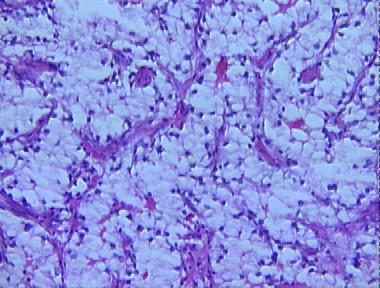

metastatic renal cell carcinoma

Histologic Features